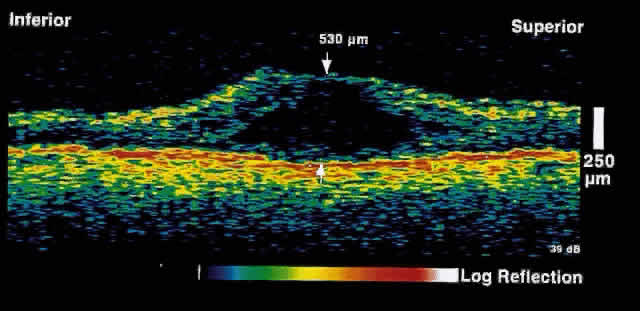

choriocapillaris/RPE layer.  Fig. 2. OCT image shows a neurosensory detachment secondary to central serous chorioretinopathy. The

difference in optical reflectivity between the posterior

boundary of the neurosensory retina and the underlying serous

fluid allows even small areas of elevation to be detected. Fig. 2. OCT image shows a neurosensory detachment secondary to central serous chorioretinopathy. The

difference in optical reflectivity between the posterior

boundary of the neurosensory retina and the underlying serous

fluid allows even small areas of elevation to be detected.

Fig. 3. Several weeks later, an OCT taken through the same area reveals partial

resolution of the neurosensory detachment. Fig. 3. Several weeks later, an OCT taken through the same area reveals partial

resolution of the neurosensory detachment.